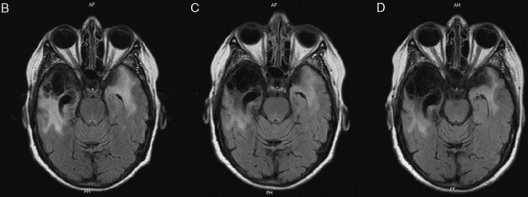

MRI of the patient.

Whipple disease is a rare, chronic multisystem infectious disease. The central nervous system (CNS) is secondarily involved in 43% of patients; 5% of patients have isolated or primary CNS involvement. The most frequent CNS symptoms are cognitive changes. Prosopagnosia is an inability to recognize familiar faces, in a person who does not have vision impairments or cognitive alterations. This relatively rare condition is usually related to vascular, traumatic, degenerative, or infectious lesions. We report a 54-year-old woman who presented subacutely with fever, headache, and seizures that led to a diagnosis of infectious meningoencephalitis. She improved temporarily on broad-spectrum antibiotics, but then developed a chronically evolving cognitive impairment with associative prosopagnosia as the major complaint. She had a history of sporadic abdominal pain and mild sacroiliac arthralgia. After a negative duodenal biopsy, we confirmed primary CNS Whipple disease by polymerase chain reaction and brain biopsy. We treated the patient with ceftriaxone for 15 days and then co-trimoxazole for 2 years. At 8-year follow-up, she had no further impairments, but continuing prosopagnosia. To our knowledge, this is the first description of isolated prosopagnosia in a patient with primary CNS Whipple disease. Because CNS Whipple disease can lead to serious, irreversible lesions if not promptly treated, clinicians must suspect the diagnosis, treat with long-term antibiotics, and follow patients carefully to prevent recurrence.